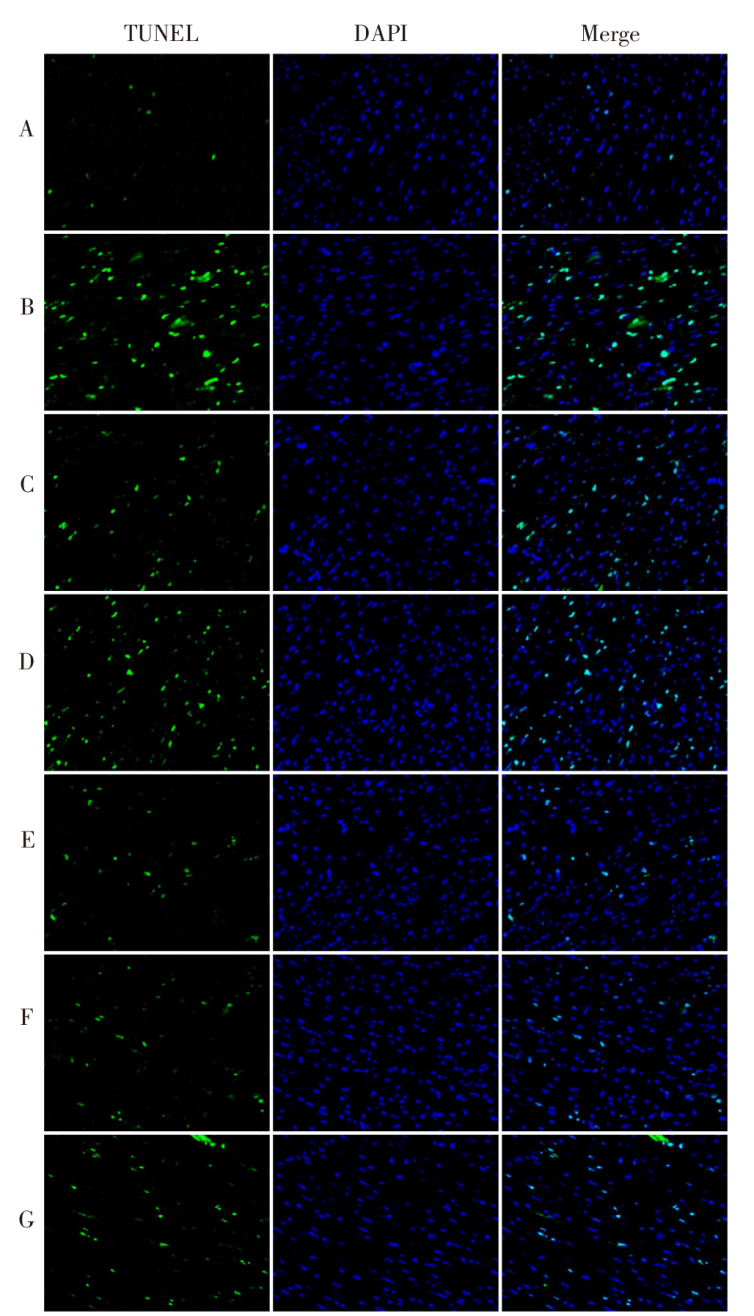

图3 TUNEL染色观察各组心房组织心肌细胞凋亡情况(×200) A—G分别为对照组、AF组、维拉帕米组、炙甘草汤-L组、炙甘草汤-H组、炙甘草汤-H+anti-NC组、炙甘草汤-H+anti-miR-26b-5p组。

Fig.3 Apoptosis of cardiomyocytes in atrial tissue observed by TUNEL staining (×200)

| 组别 | 细胞凋亡率/% | BAX/β-actin | C-caspase3/β-actin |

|---|---|---|---|

| 对照组 | 3.11±0.37 | 0.33±0.04 | 0.28±0.04 |

| AF组 | 29.84±3.15a | 0.89±0.10a | 0.83±0.09a |

| 维拉帕米组 | 10.17±1.21b | 0.42±0.05b | 0.35±0.05b |

| 炙甘草汤-L组 | 20.49±2.24b | 0.69±0.08b | 0.63±0.07b |

| 炙甘草汤-H组 | 7.65±0.83bc | 0.37±0.05bc | 0.31±0.04bc |

| 炙甘草汤-H+anti-NC组 | 8.33±0.89 | 0.39±0.05 | 0.32±0.04 |

| 炙甘草汤-H+ anti-miR-26b-5p组 | 16.21±1.75d | 0.65±0.08d | 0.59±0.07d |

| F | 166.978* | 58.539* | 74.484* |

表4 各组大鼠心房组织心肌细胞凋亡情况比较

Tab.4 Comparison of cardiomyocyte apoptosis in atrial tissue between different groups of rats (n=6,$\bar{x}±s$)